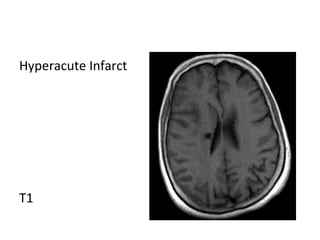

Hyperacute Infarct

T1

T2